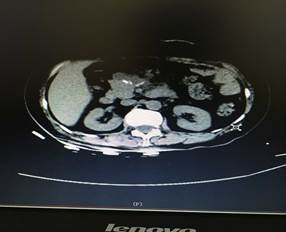

充分術(shù)前準(zhǔn)備后,在肝膽外科團(tuán)隊(duì)努力及麻醉科的鼎力支持下,歷經(jīng)4個(gè)多小時(shí),大家成功在腹腔鏡下為患者進(jìn)行了胰腺巨大腫瘤及胰腺體尾端切除,脾臟、膽囊切除手術(shù)。術(shù)后第四天患者便進(jìn)食流汁,下床活動(dòng),復(fù)查情況良好(圖2、圖3),患者和家屬臉上都露出了久違的笑容。

圖2

圖3